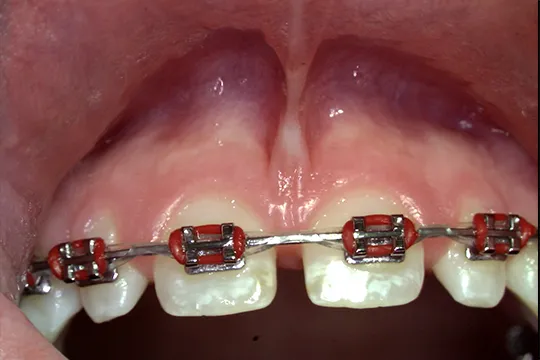

Frenectomy

After